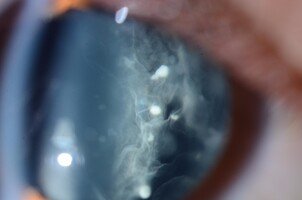

Imágenes

Banco de nieve.

En los niños puede haber una inflamación en segmento anterior importante que lleve a la formación de sinequias posteriores y tardíamente queratopatía en banda. En jóvenes en cambio, es infrecuente tener inflamación del segmento anterior y lo que se encuentran son precipitados queráticos estrellados, finos y difusos como en la uveítis de Fuchs, con Tyndall de +1-2. La córnea puede estar afectada en la forma de endotelitis.